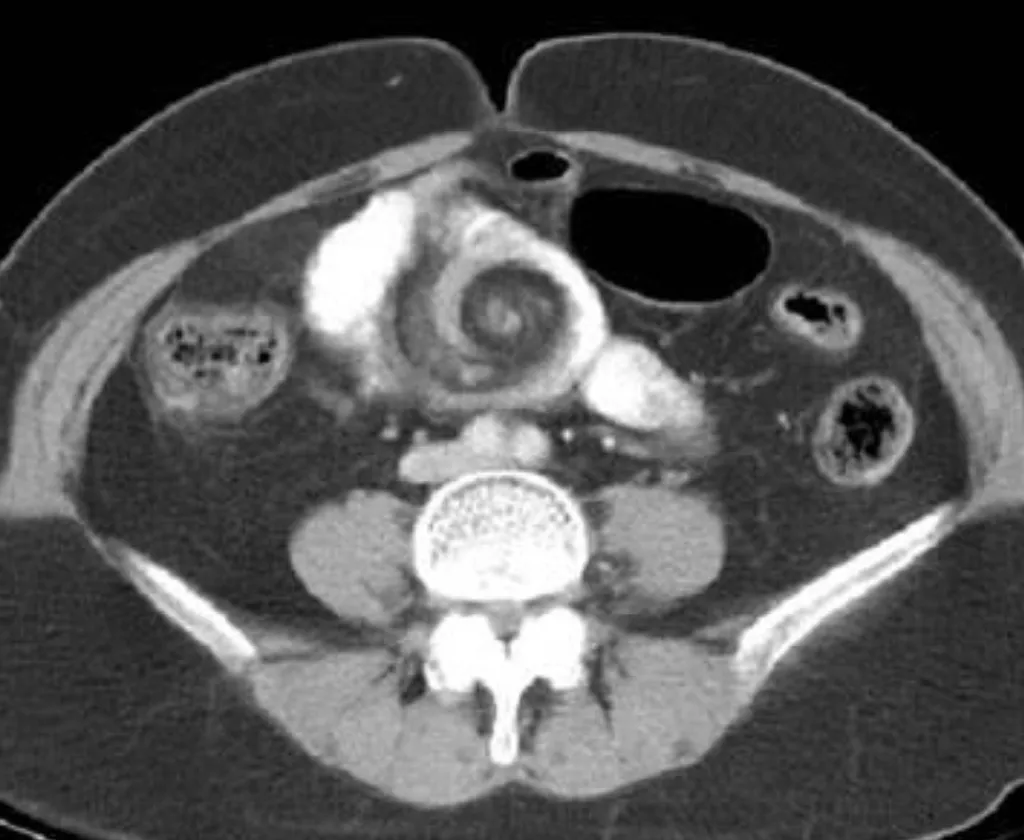

【114-2 醫學(五) 第74題】病人主訴腹脹、反胃及腹部悶痛;腹部電腦斷層檢查呈現如附圖。下列何項初診斷最恰當?

詳解

破題關鍵

這張電腦斷層影像最關鍵的線索是腹部中央出現的「旋渦狀」(whirl sign),這是腸道和腸繫膜血管扭轉的典型表現,直接指向腸扭轉。